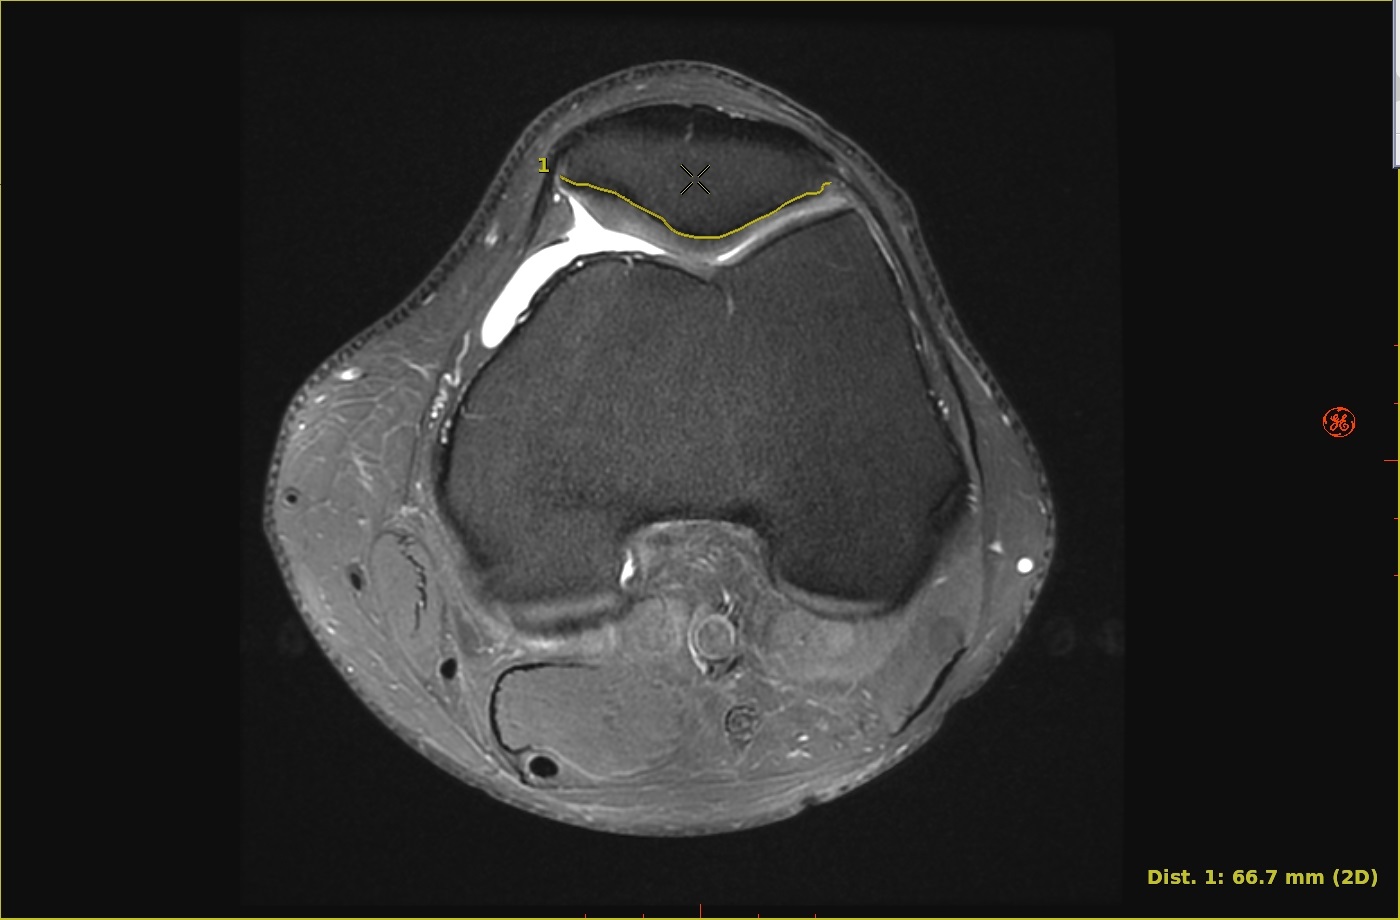

Use these steps to create a curved distance measurement.Figure 1. Curved measurement